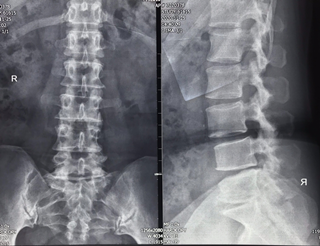

患者腰椎X片及MRI